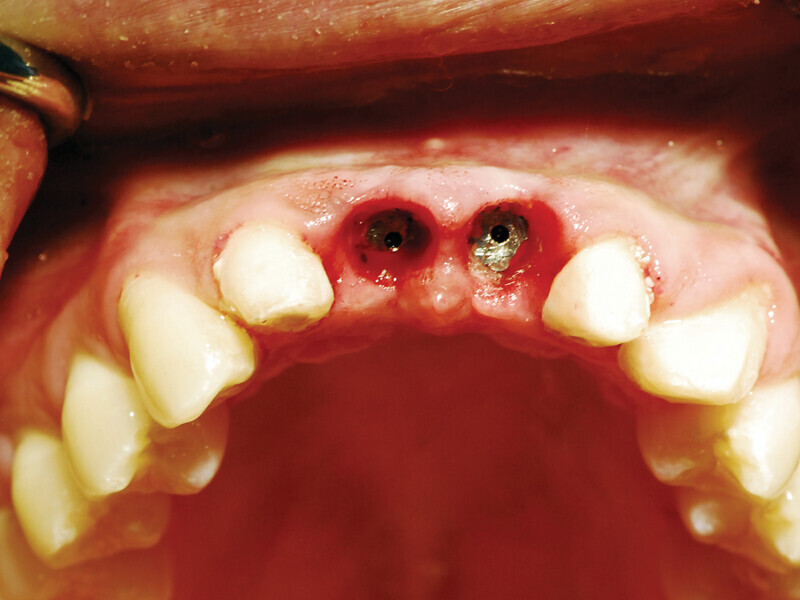

Fig. 8: Picasso Lite+ diode laser removing soft tissue to uncover the implants’ cover screws. (Photo provided by Dr. Gregori M. Kurtzman)

Fig. 9: Uncovery of the implants and healing screws exposed. (Photo provided by Dr. Gregori M. Kurtzman)